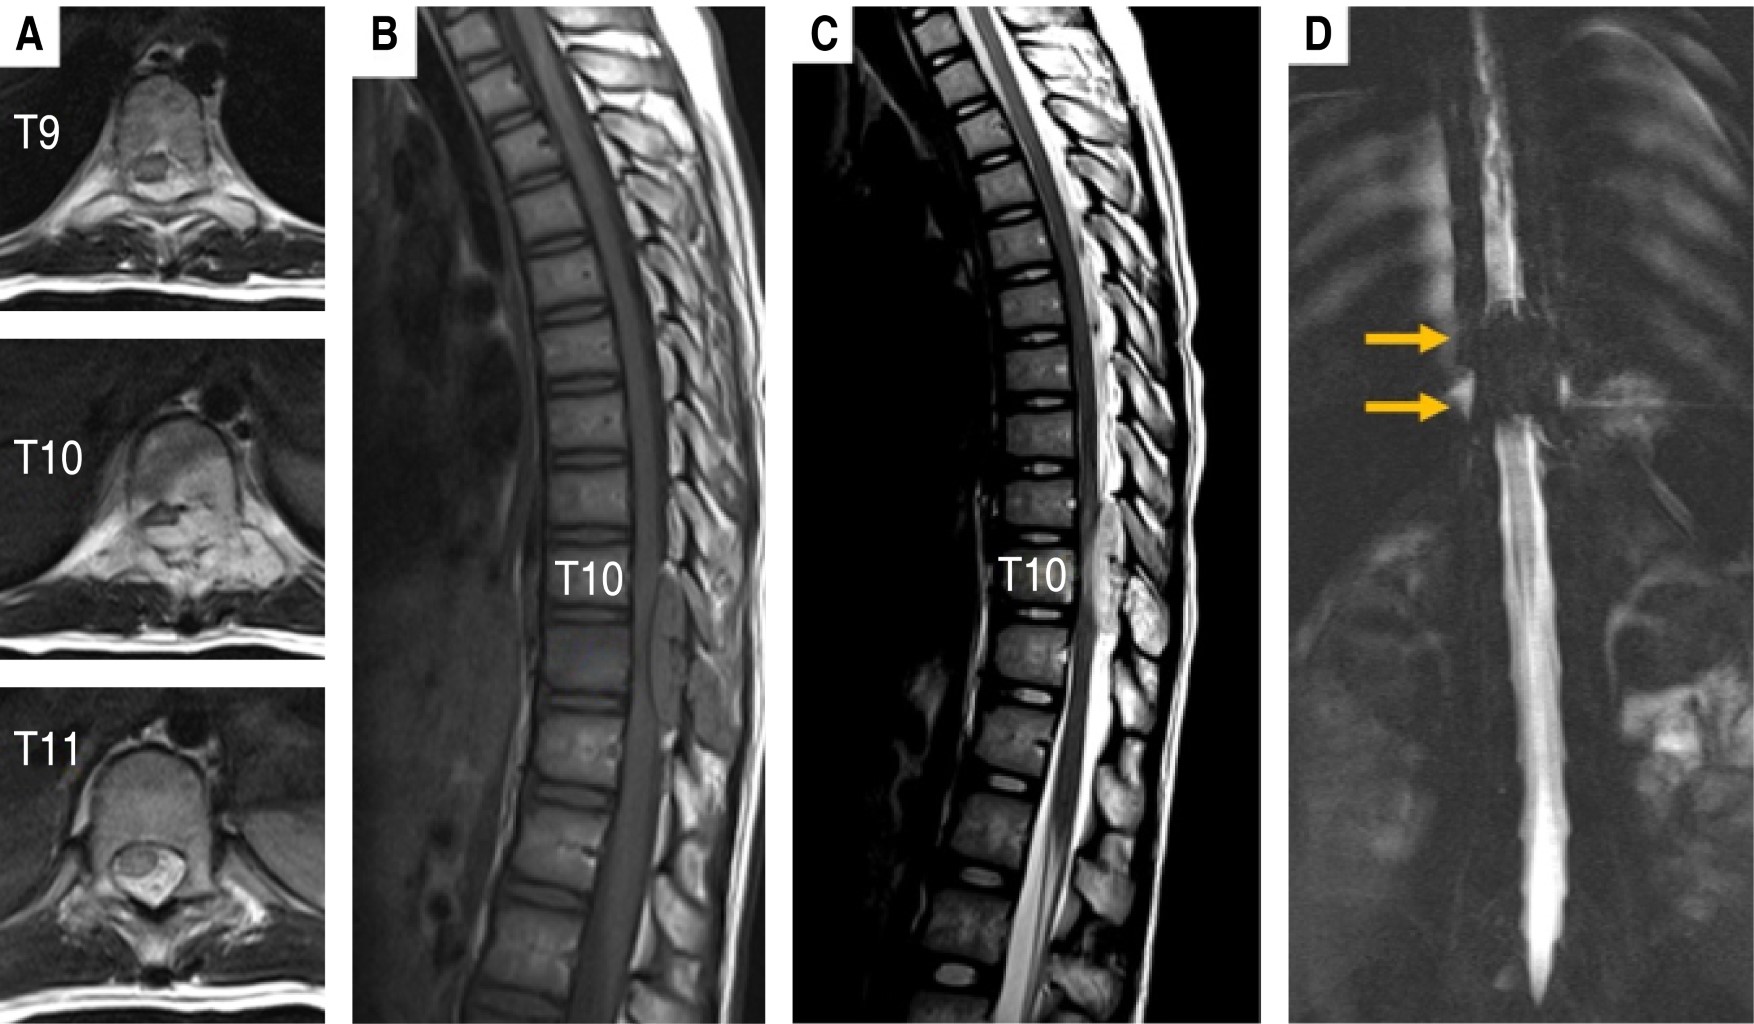

Figure 1